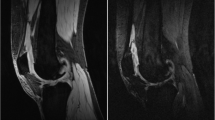

Example post-contrast 3D FS SPGR images overlaid with Ktrans data from participants with increases (a) and decreases (b) in Ktrans at 6 months which exceeds the SDD. In a, note extruded medial meniscus with cuff of adjacent synovitis (white arrow). At 6 months, the synovitis has increased both in amount and intensity. In b, note distention of suprapatellar pouch (white arrow) and synovitis adjacent to the anterior horn of lateral meniscus (white arrowhead) at baseline, with marked reduction at 6 months